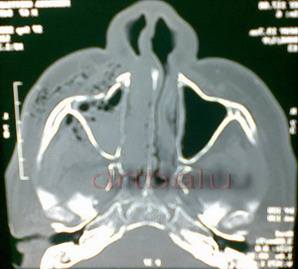

CT scan both axial and coronal sections of paranasal sinuses is diagnostic.

Axial CT PNS showing fracture of anterior wall of maxilla and zygoma